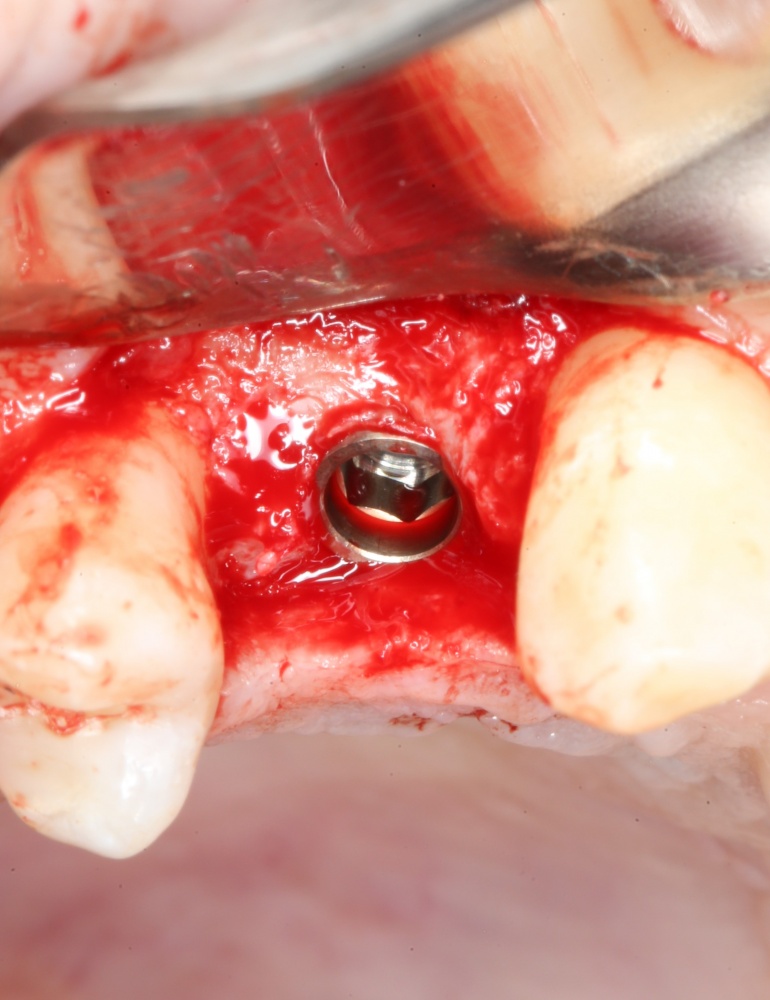

Важный момент! Если вы сделали всё правильно, подготовленная лунка должна кровоточить, а имплантат без вращения должен проваливаться в неё,как минимум, наполовину вне зависимости от его длины:

Поскольку на устанавливаемом нами имплантате уже зафиксирован временный абатмент TempBase, мы используем соответствующий гексагональный ключ 3.4/TB.

Устанавливаем имплантат с усилием не более 30 Нсм. График торка, записанный диспенсером, выглядит как-то так: